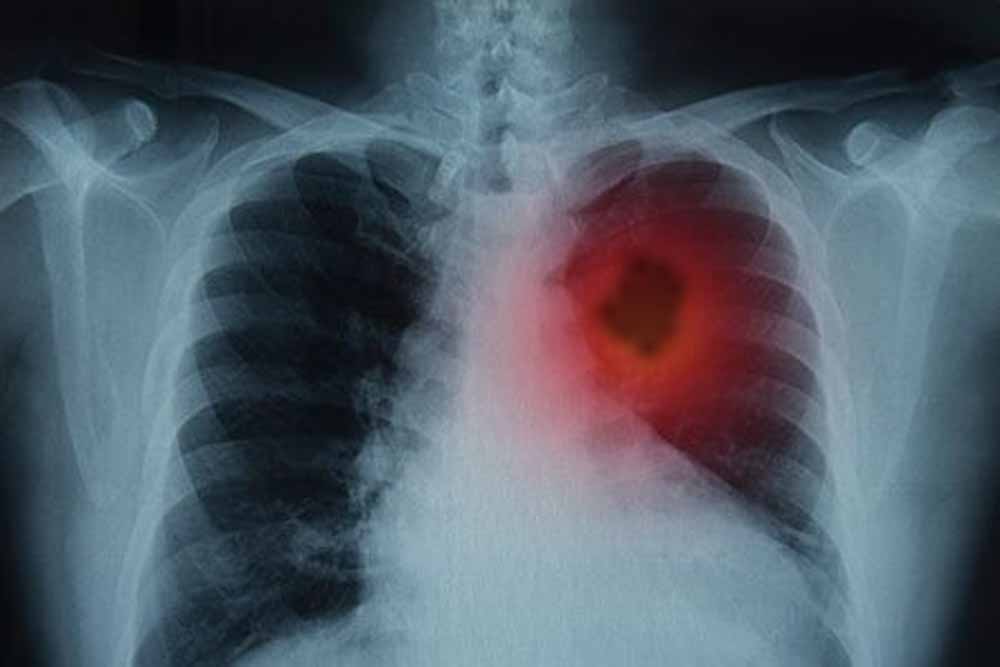

फेफड़ों के कैंसर से लड़ाई में नई उम्मीद! शोध में ट्यूमर 80% तक कम करने की सफलता

फेफड़ों के कैंसर से जूझ रहे लाखों लोगों के लिए विज्ञान की दुनिया से एक बहुत बड़ी और राहत भरी खबर आई है। दरअसल, वैज्ञानिकों ने एक ऐसा तरीका खोजा है जिससे फेफड़ों के ट्यूमर को उसकी सबसे बड़ी कमजोरी पर वार करके खत्म किया जा सकता है। जी हां, इस शोध के दौरान, उन्होंने एक बेहद जरूरी प्रोटीन की पहचान की। बता दें, यह प्रोटीन कैंसर कोशिकाओं को 'मरने' से बचाता है। ऐसे में, शोधकर्ताओं का कहना है कि अगर इस खास प्रोटीन की गतिविधि को रोक दिया जाए, तो कैंसर कोशिकाएं खुद-ब-खुद नष्ट होने लगती हैं और ट्यूमर सिकुड़ जाता है।

हाल ही में शोधकर्ताओं ने फेफड़ों के कैंसर की एक महत्वपूर्ण कमजोरी का पता लगाया है- एक ऐसा प्रोटीन, जिसे रोक दिया जाए तो कैंसर कोशिकाएं खुद को ही नष्ट करने लगती हैं। यह खोज न सिर्फ इलाज के नए रास्ते खोलती है, बल्कि भविष्य में ऐसे कई मरीजों के लिए जीवनदायिनी साबित हो सकती है, जिन्हें अब तक सीमित विकल्प ही उपलब्ध थे।